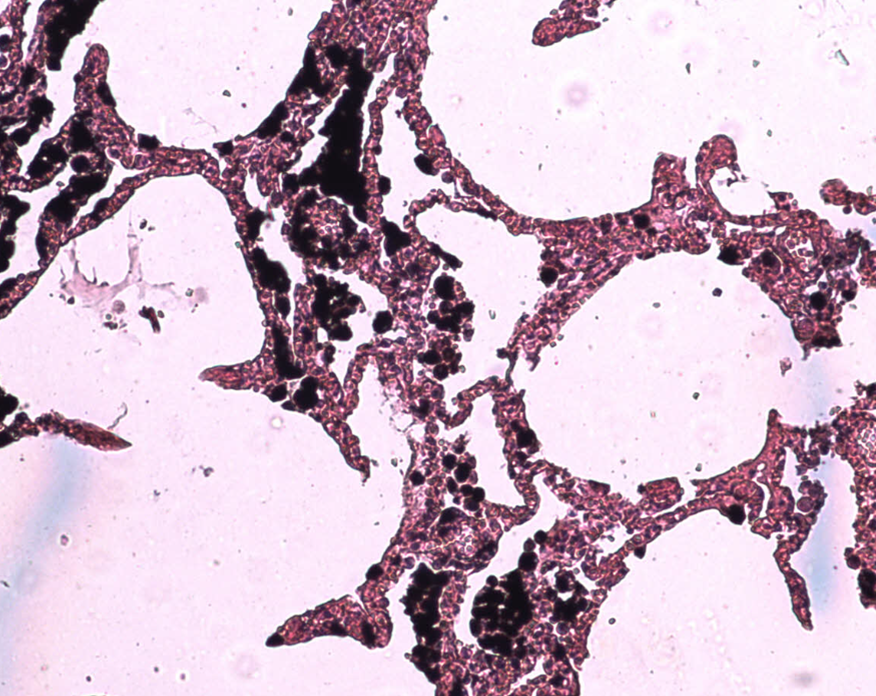

Homo sapiens - Człowiek rozumny - Płuco zdrowego człowieka